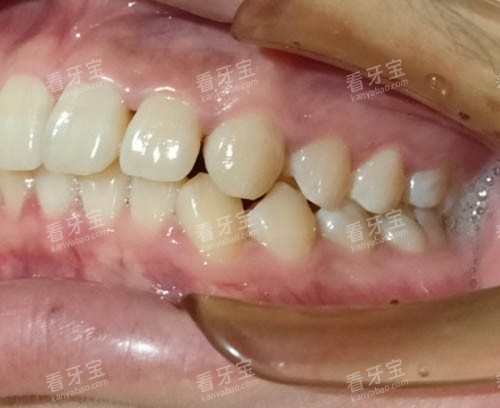

正畸科的赵艳管理者则是隐形矫正达人,她主导的青少年早期干预系统已帮助1200多名孩子避免拔牙矫正。

隐形矫正:悄悄变漂亮的黑科技

引进美国iTero口扫仪,5分钟就能生成牙齿3D模型,患者可实时看到矫正后的结果。

牙齿矫正:隐形矫正占比超60%

金属自锁托槽:8800元起

时代天使冠军版:25800元

舌侧矫正:50000元